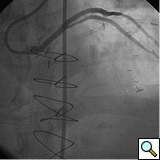

PCI of the vein and arterial grafts have unique challenges. For any PCI, guide support is very important for successful balloon and stent delivery. In a tortuous vein graft with a steep angle, advancement of a stent can be very difficult and challenging. Therefore, it is important to choose the best available catheter before starting PCI. Similar to the right coronary angiography, a JR4 guide catheter is most commonly used in this setting. However, Amplatz guide catheters for left vein grafts and multipurpose catheters for right vein grafts are better choices in certain anatomy. In Figure 8 and Figure 10 two examples of poor guide support in two vein graft interventions can be seen. Initially, a JR4 guide was used for PCI of the vein graft supplying the left anterior descending artery (LAD) without any success. However, after changing the guide to an Amplatz left 2 guide catheter, we achieved excellent support without any difficulty in advancing two stents (Figure 9). In Figure 10, difficulty is illustrated in engaging the vein graft ostium supplying the right coronary artery with a JR4 catheter. This vein graft has a very steep inferior take off from the aorta. After changing the guide to a multipurpose catheter, we were able to deliver three stents successfully without any difficulties (Figure 11). Similar challenges exist in the treatment of the left IMA or right IMA. These arterial grafts can be extremely tortuous making stent delivery very difficult. It may be necessary to use short length stents for a better deliverability or stents with lowest profile. Usually, similar to the native coronary intervention, a 6 French guide is appropriate for the routine use.

In order to minimize distal embolization, primary stenting without previous angioplasty is recommended in vein graft interventions. However, in angulated and very high grade lesions, stent without balloon angioplasty may not be able to cross a lesion requiring balloon angioplasty before stenting. Balloons should be sized smaller in order to prevent rupture or dissection. Once an angioplasty balloon is advanced across the lesion, usually it is inflated to 6 or 8 atmospheres for few seconds. Stenting is similar to the balloon. Once a stent is placed across the lesion, it is inflated to higher pressures such as 12-14 atmospheres. The use of a bare metal or drug eluting stents in vein grafts is controversy. This topic is discussed in detail in the restenosis chapter. Angioplasty and stenting of bifurcation sequential vein grafts at the site of the bifurcation or distal to the graft is challenging and usually requires more complex interventions including double wiring and utilization of two stents. A comprehensive classification with guide to interventional techniques for bifurcation lesions is published recently that can be used as a guide for bifurcation lesions interventions involving vein grafts [1].